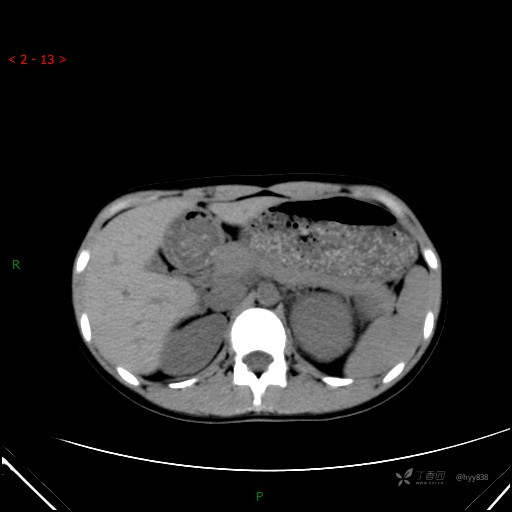

增强动脉期